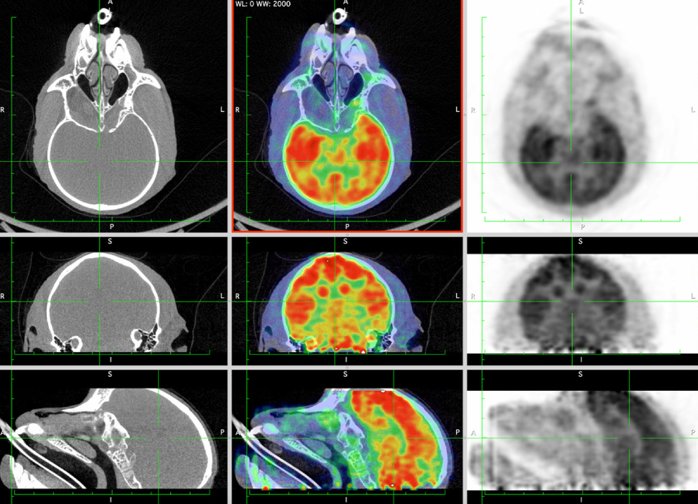

CASE 4: NHP brain PET/CT dynamic DOPA imaging

• Courtesy of: CERMEP, Lyon, France

Research objective: Investigation of DOPA uptake in NHP brain

Animal model: NHP, ~ 3 kg

Acquisition protocol: PET imaging: 90 min acquisition, injection right after acquisition starts. CT imaging: 80kV, 40s

Processing and reconstruction protocol: PET: 3D OSEM, 9x 10 min, 0.84 mm isotropic voxel size. CT: 0.15 mm isotropic voxel size

Biomarker or contrast agent: 18F-DOPA, ~ 3 mCi